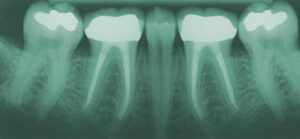

root canals

Rescue your tooth with a root canal

Root canals can repair your decayed or damaged tooth and save it, so that it doesn’t have to be removed.

Our teeth are made up of several parts, including the crown — the white part of the tooth above the gums — and the root below the gums, which contains pulp, which is the soft tissue inside your tooth. This soft tissue contains blood vessels and nerves, and also provides nourishment for healthy teeth. Without proper care — or as the result of trauma to the tooth — this pulp can become infected. Once your tooth is infected, you may experience swelling and pain near the site, and you’re at risk of losing your tooth completely due to bacterial damage to the bone surrounding your tooth.

A root canal is a procedure to clean the canals of your tooth root in order to save the tooth and seal against future decay.

Root canal treatments typically take one or two additional office visits to complete. We will use local anesthesia to keep the procedure painless and easy for you. Before beginning, we’ll take x-rays of your tooth and the bone surrounding it, numb you with the local anesthesia, and apply a thin rubber sheet over your tooth to protect it and keep it dry during the procedure.